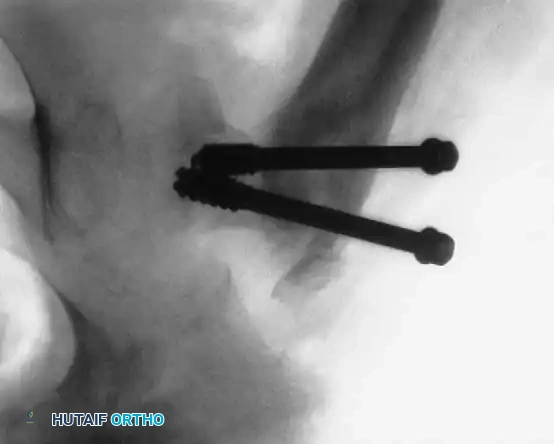

- Fixation: In older children, cannulated hip screws can be used. However, in infants and young children, crossing the physis with threaded screws will cause premature physeal closure and severe leg-length discrepancy.

- Technique: Use specially manufactured smooth pins (unthreaded) to secure the epiphysis. Note that smooth pins lack compression and may migrate; therefore, postoperative spica casting is mandatory.

Fig. 8: Type I transepiphyseal separation treated with closed reduction and fixation using cannulated hip screws in an older child.

Fig. 9: Intraoperative fluoroscopy confirming pin placement across the physis.